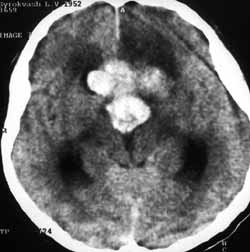

Рис. 9. Кровоизлиянии в аденому гипофиза.